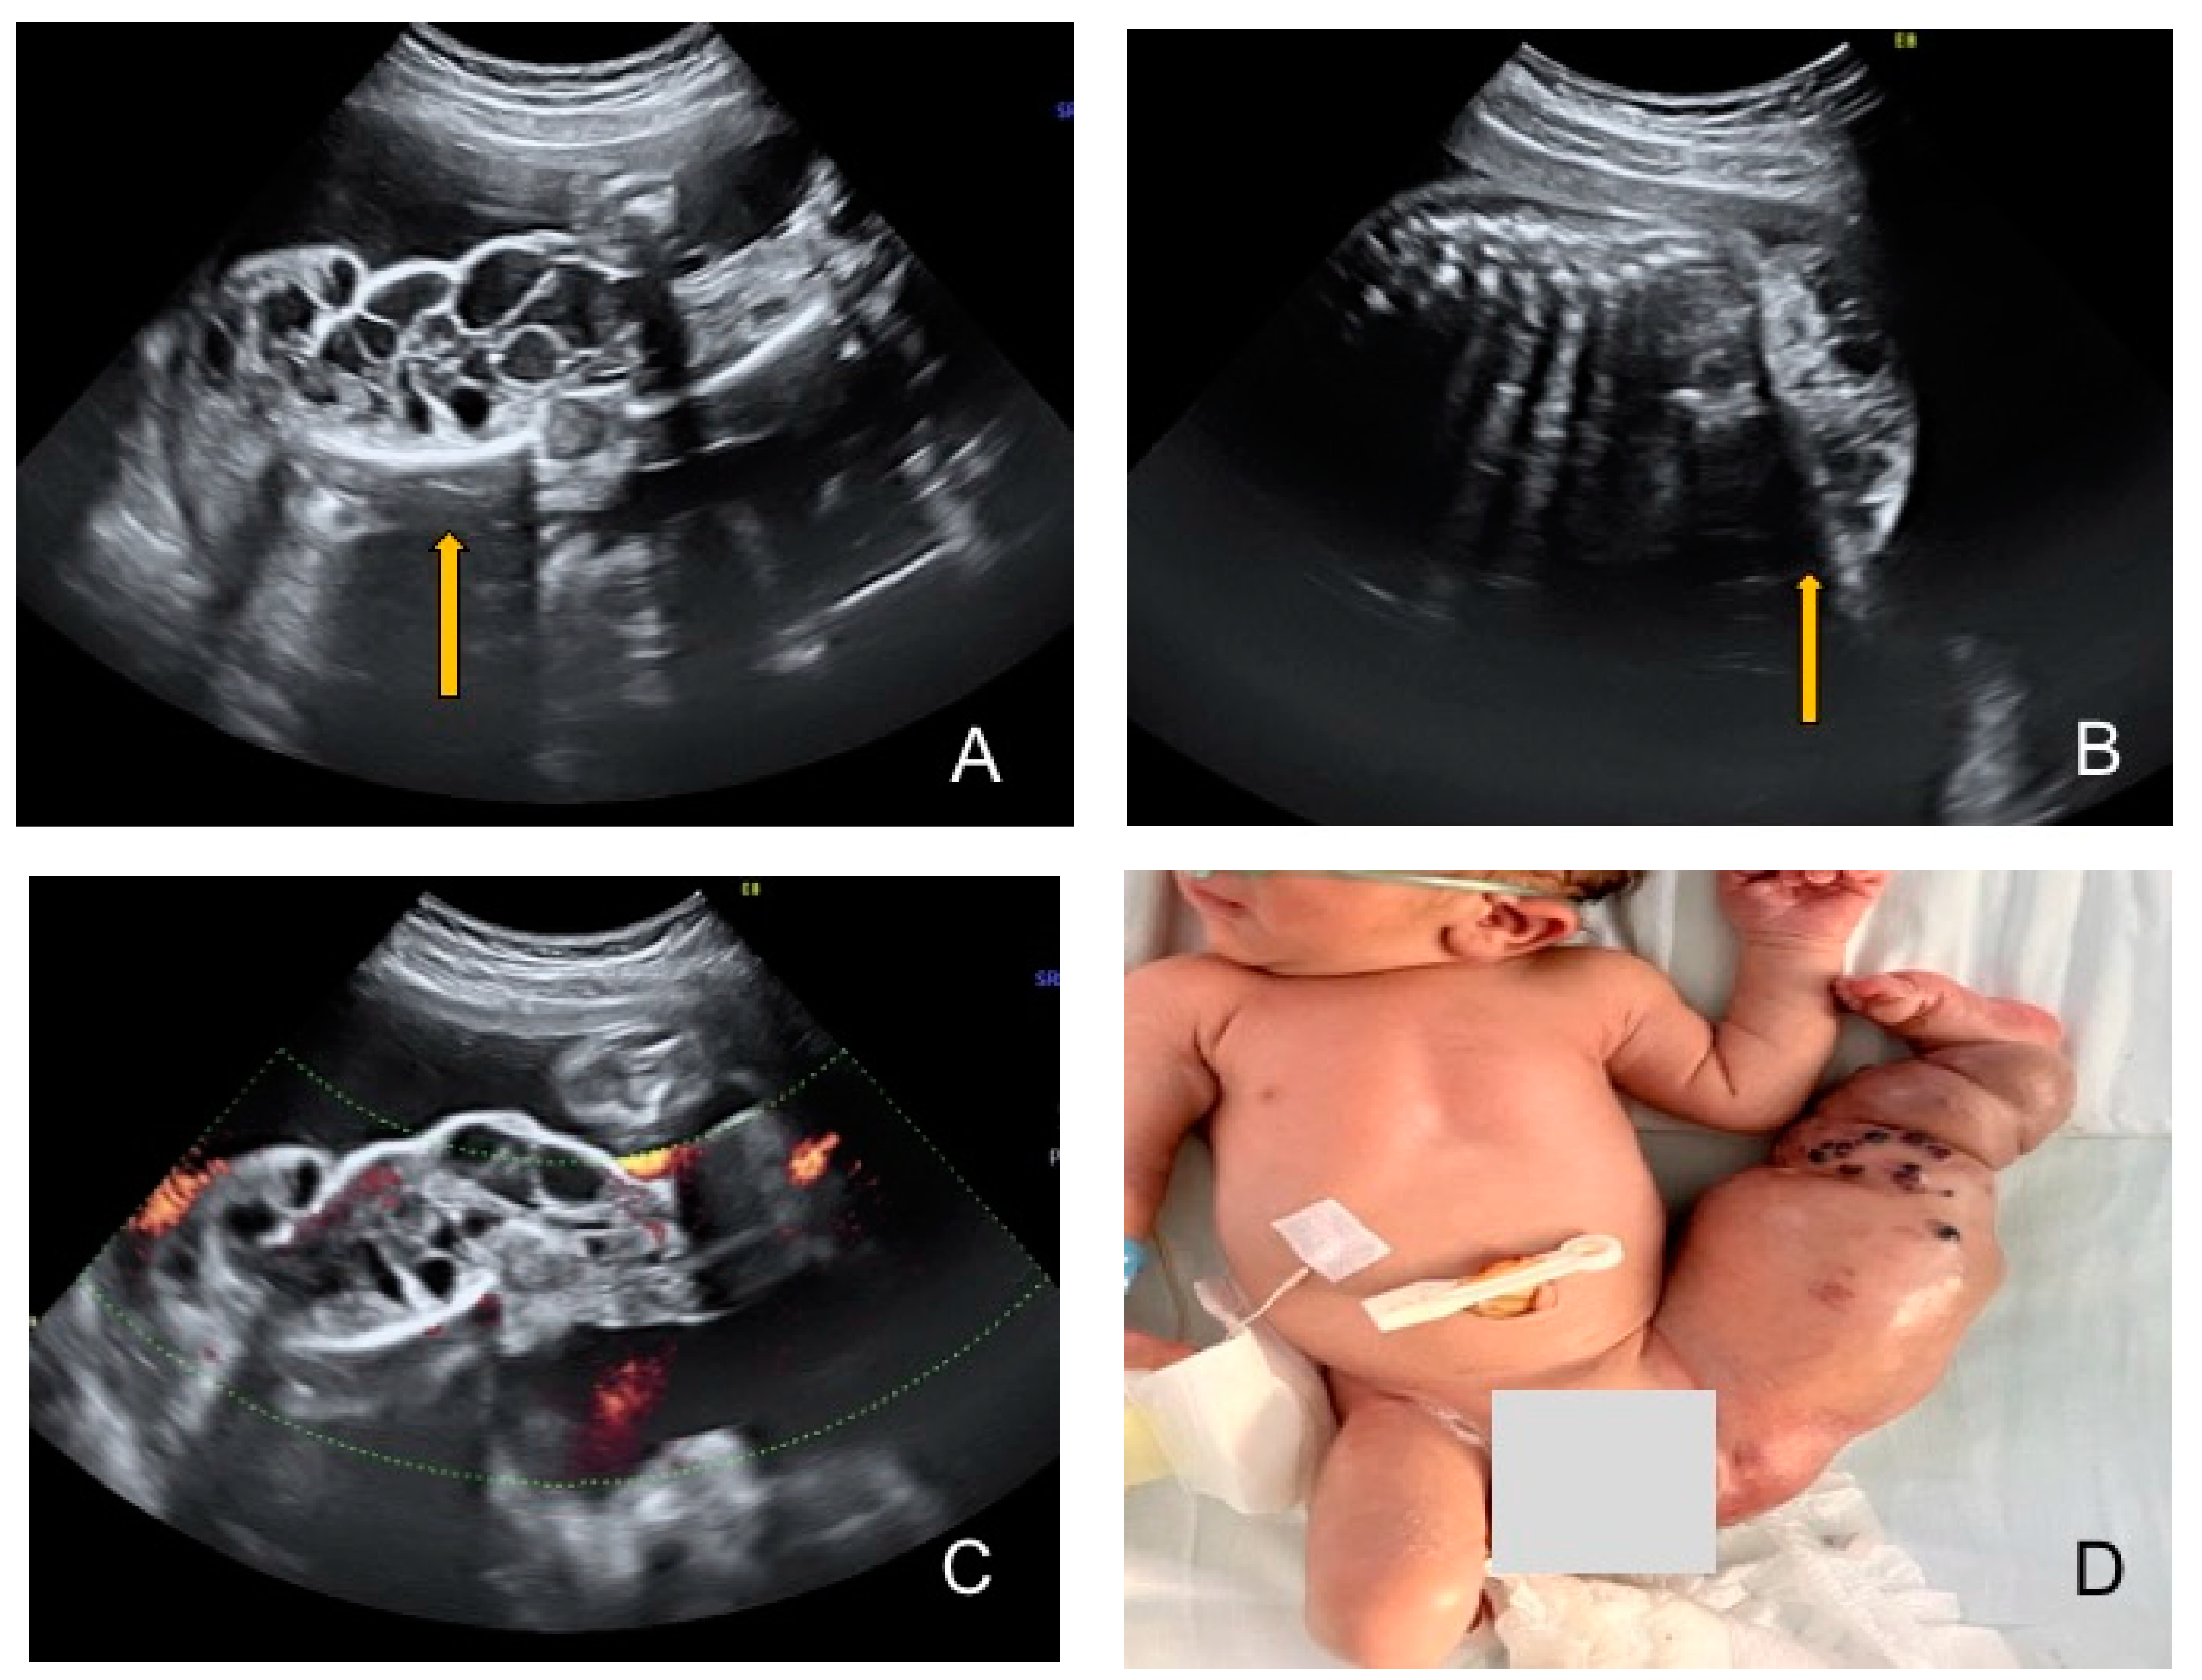

Prenatal Ultrasound Diagnosis of Klippel–Trenaunay Syndrome